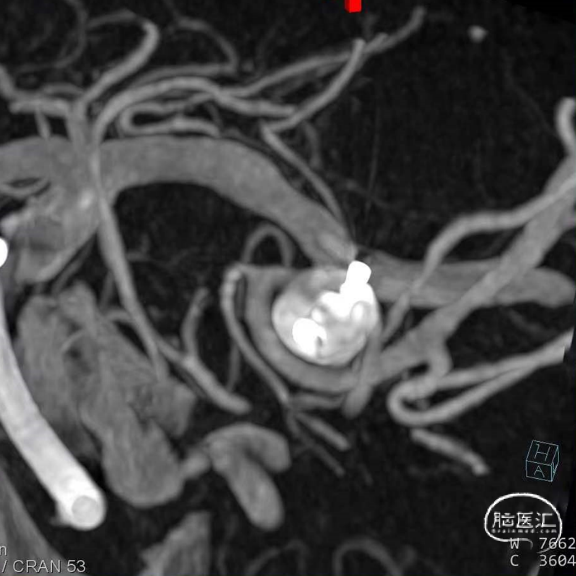

经造影可见WEB™尺寸合适,贴合瘤壁,小脑上动脉分支,大脑后动脉分支等血流通畅。解脱后,再次造影和Dyna-CT评估,可见动脉瘤瘤腔内有明显造影剂滞留,小脑上动脉瘤显影良好,分支血管血流正常。

经造影可见WEB™尺寸合适,贴合瘤壁,覆盖瘤颈,且下支M2段分支及其他分支血管血流通畅。

解脱后,再次造影和Dyna-CT评估,可见动脉瘤瘤腔内有明显造影剂滞留,分支血管血流正常。